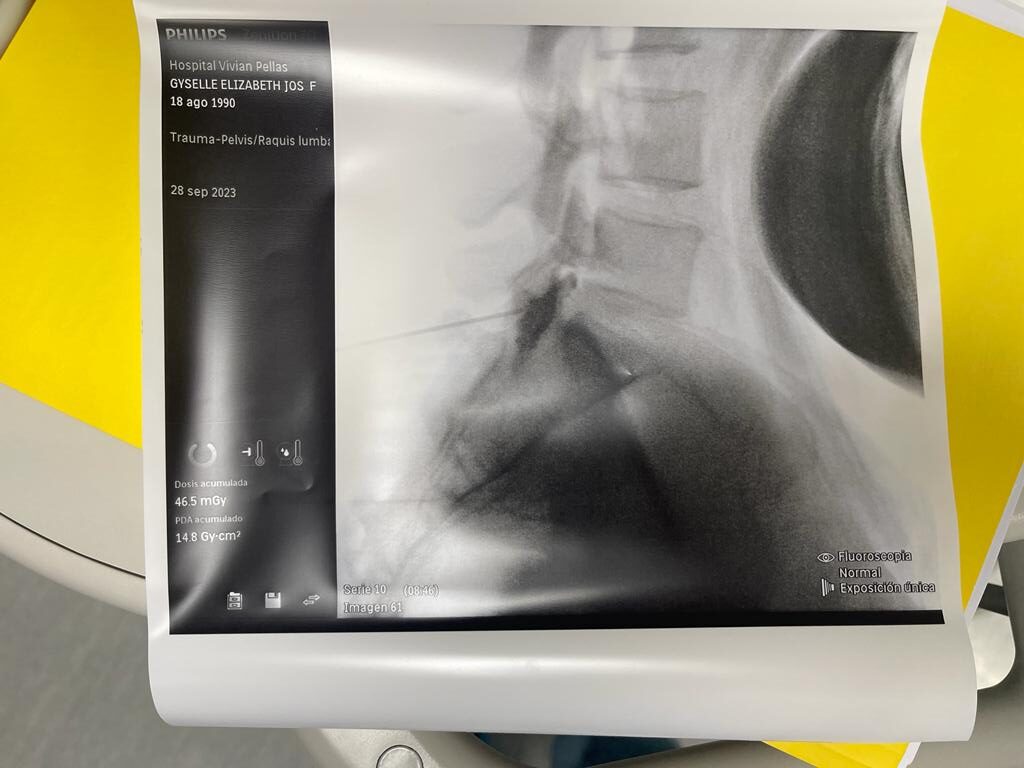

Rizólisis (Ablación por Radiofrecuencia)

Técnica mínimamente invasiva para tratar el dolor crónico articular de la columna

¿Qué es?

La rizólisis es un procedimiento no quirúrgico que utiliza energía de radiofrecuencia para inactivar de forma selectiva los nervios responsables de transmitir dolor desde las articulaciones facetarias de la columna.

¿Para quién está indicada?